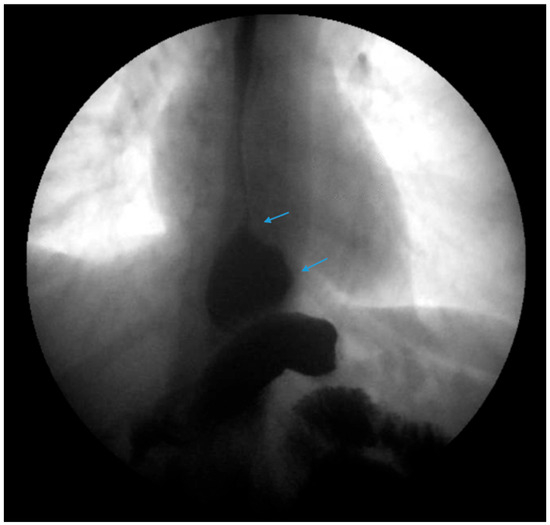

Figure 7.

An upper gastrointestinal series reveals a small, sliding hiatal hernia (bottom arrow) in addition to gastroesophageal reflux disease (top arrow) in a patient following sleeve gastrectomy.

Figure 8.

An upper gastrointestinal series reveals a small, sliding hiatal hernia (bottom arrow) with spontaneous gastroesophageal reflux (top arrow) in a patient following sleeve gastrectomy.